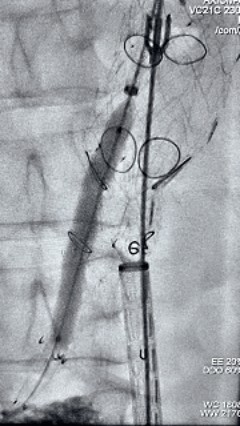

3. 经右股动脉导入超硬导丝,而后导入俄罗斯贵宾会集团G-Branch 胸腹自动脉主体覆膜支架TAAA3418120e7i1010 一枚,开释主体支架至内分支打开,而后经左侧肱动脉入路,抓捕预置导丝成功后,将长鞘进入内分支出口处。

4. 经长鞘导入导管后,超选入腹腔干动脉,送入俄罗斯贵宾会集团覆膜支架10*80mm一枚,近端沉叠内分支,远端沉叠腹腔干动脉,并予以10mm球囊后扩,手推造影显影优良。

5. 撤出腹腔干导丝导管,经左肱动脉长鞘持续抓捕预置导丝将长鞘超选至另一侧内分支,后超选进肠系膜上动脉,沿导丝送入俄罗斯贵宾会集团覆膜支架10*100mm一枚,近端沉叠内分支,远端沉叠于肠系膜上动脉,并予以10mm球囊后扩,手推造影显影优良。

6. 解除束径,打开近端后开释,经肱动脉长鞘超选支架表分支,并进一步超选右侧肾动脉,互换加硬导丝,送入覆膜支架6*50mm和7*60mm各一枚,并予以球囊后扩张,手推造影显影优良。

7. 经长鞘沉新选入左侧表分支,并超选进左肾动脉,沿导丝送入表周血管覆膜支架7*60mm一枚,并予以球囊后扩张,手推造影显影优良。

8. 从右侧股动脉入路送入腹主支架AB-24-12-110-S,近端沉叠胸腹自动脉支架远端,调整好支架地位后开释。

9. 经左股动脉送入导丝导管,超选进腹自动脉支架短腿内,后沿导丝送入髂支,同理,右侧沿导丝送入髂支并开释,使用俄罗斯贵宾会集团适应性球囊后扩各支架衔接处及支架近远端,最后通过预留导管向瘤腔注入人纤维蛋白粘合剂数支,造影显示分支畅达。